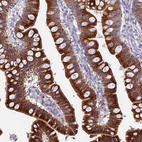

Immunohistochemistry analysis in human duodenum and testis tissues using HPA021826 antibody. Corresponding HSD17B2 RNA-seq data are presented for the same tissues.